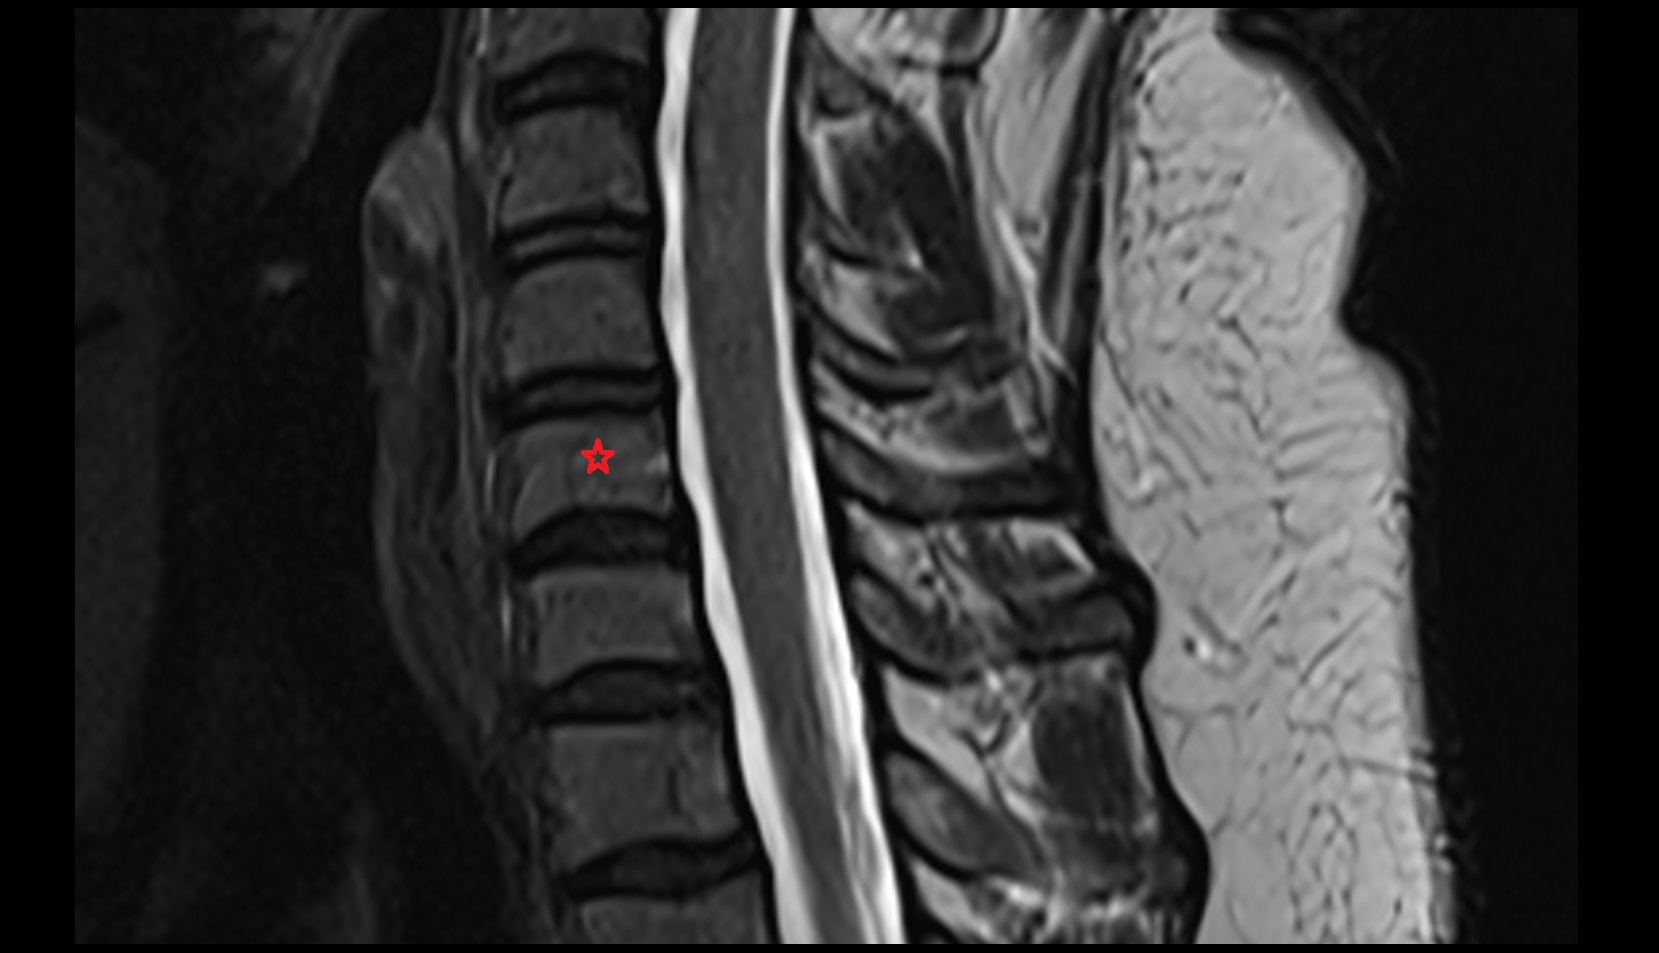

- L5–S1 Intervertebral disc

- L4–L5 Intervertebral Disc

- L3–L4 Intervertebral Disc

- L2–L3 Intervertebral Disc

- L1–L2 Intervertebral Disc